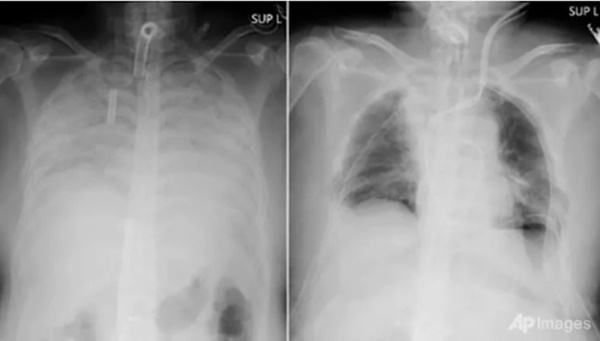

Hội chứng phổi trắng (thường được mọi người gọi là bệnh phổi trắng hay phổi khô) là chỉ tình trạng phổi có màu trắng xoá trên phim chụp X quang.

Bình thường, một lá phổi khỏe mạnh khi chụp phim X-quang, thì sẽ thấy phổi trong (hình ảnh hiển thị máu đen). Tuy nhiên, do viêm phổi hoặc bệnh lý khác dẫn đến phim phổi có hình ảnh trắng bất thường.

Hình ảnh X-quang phổi trắng (Ảnh minh họa)